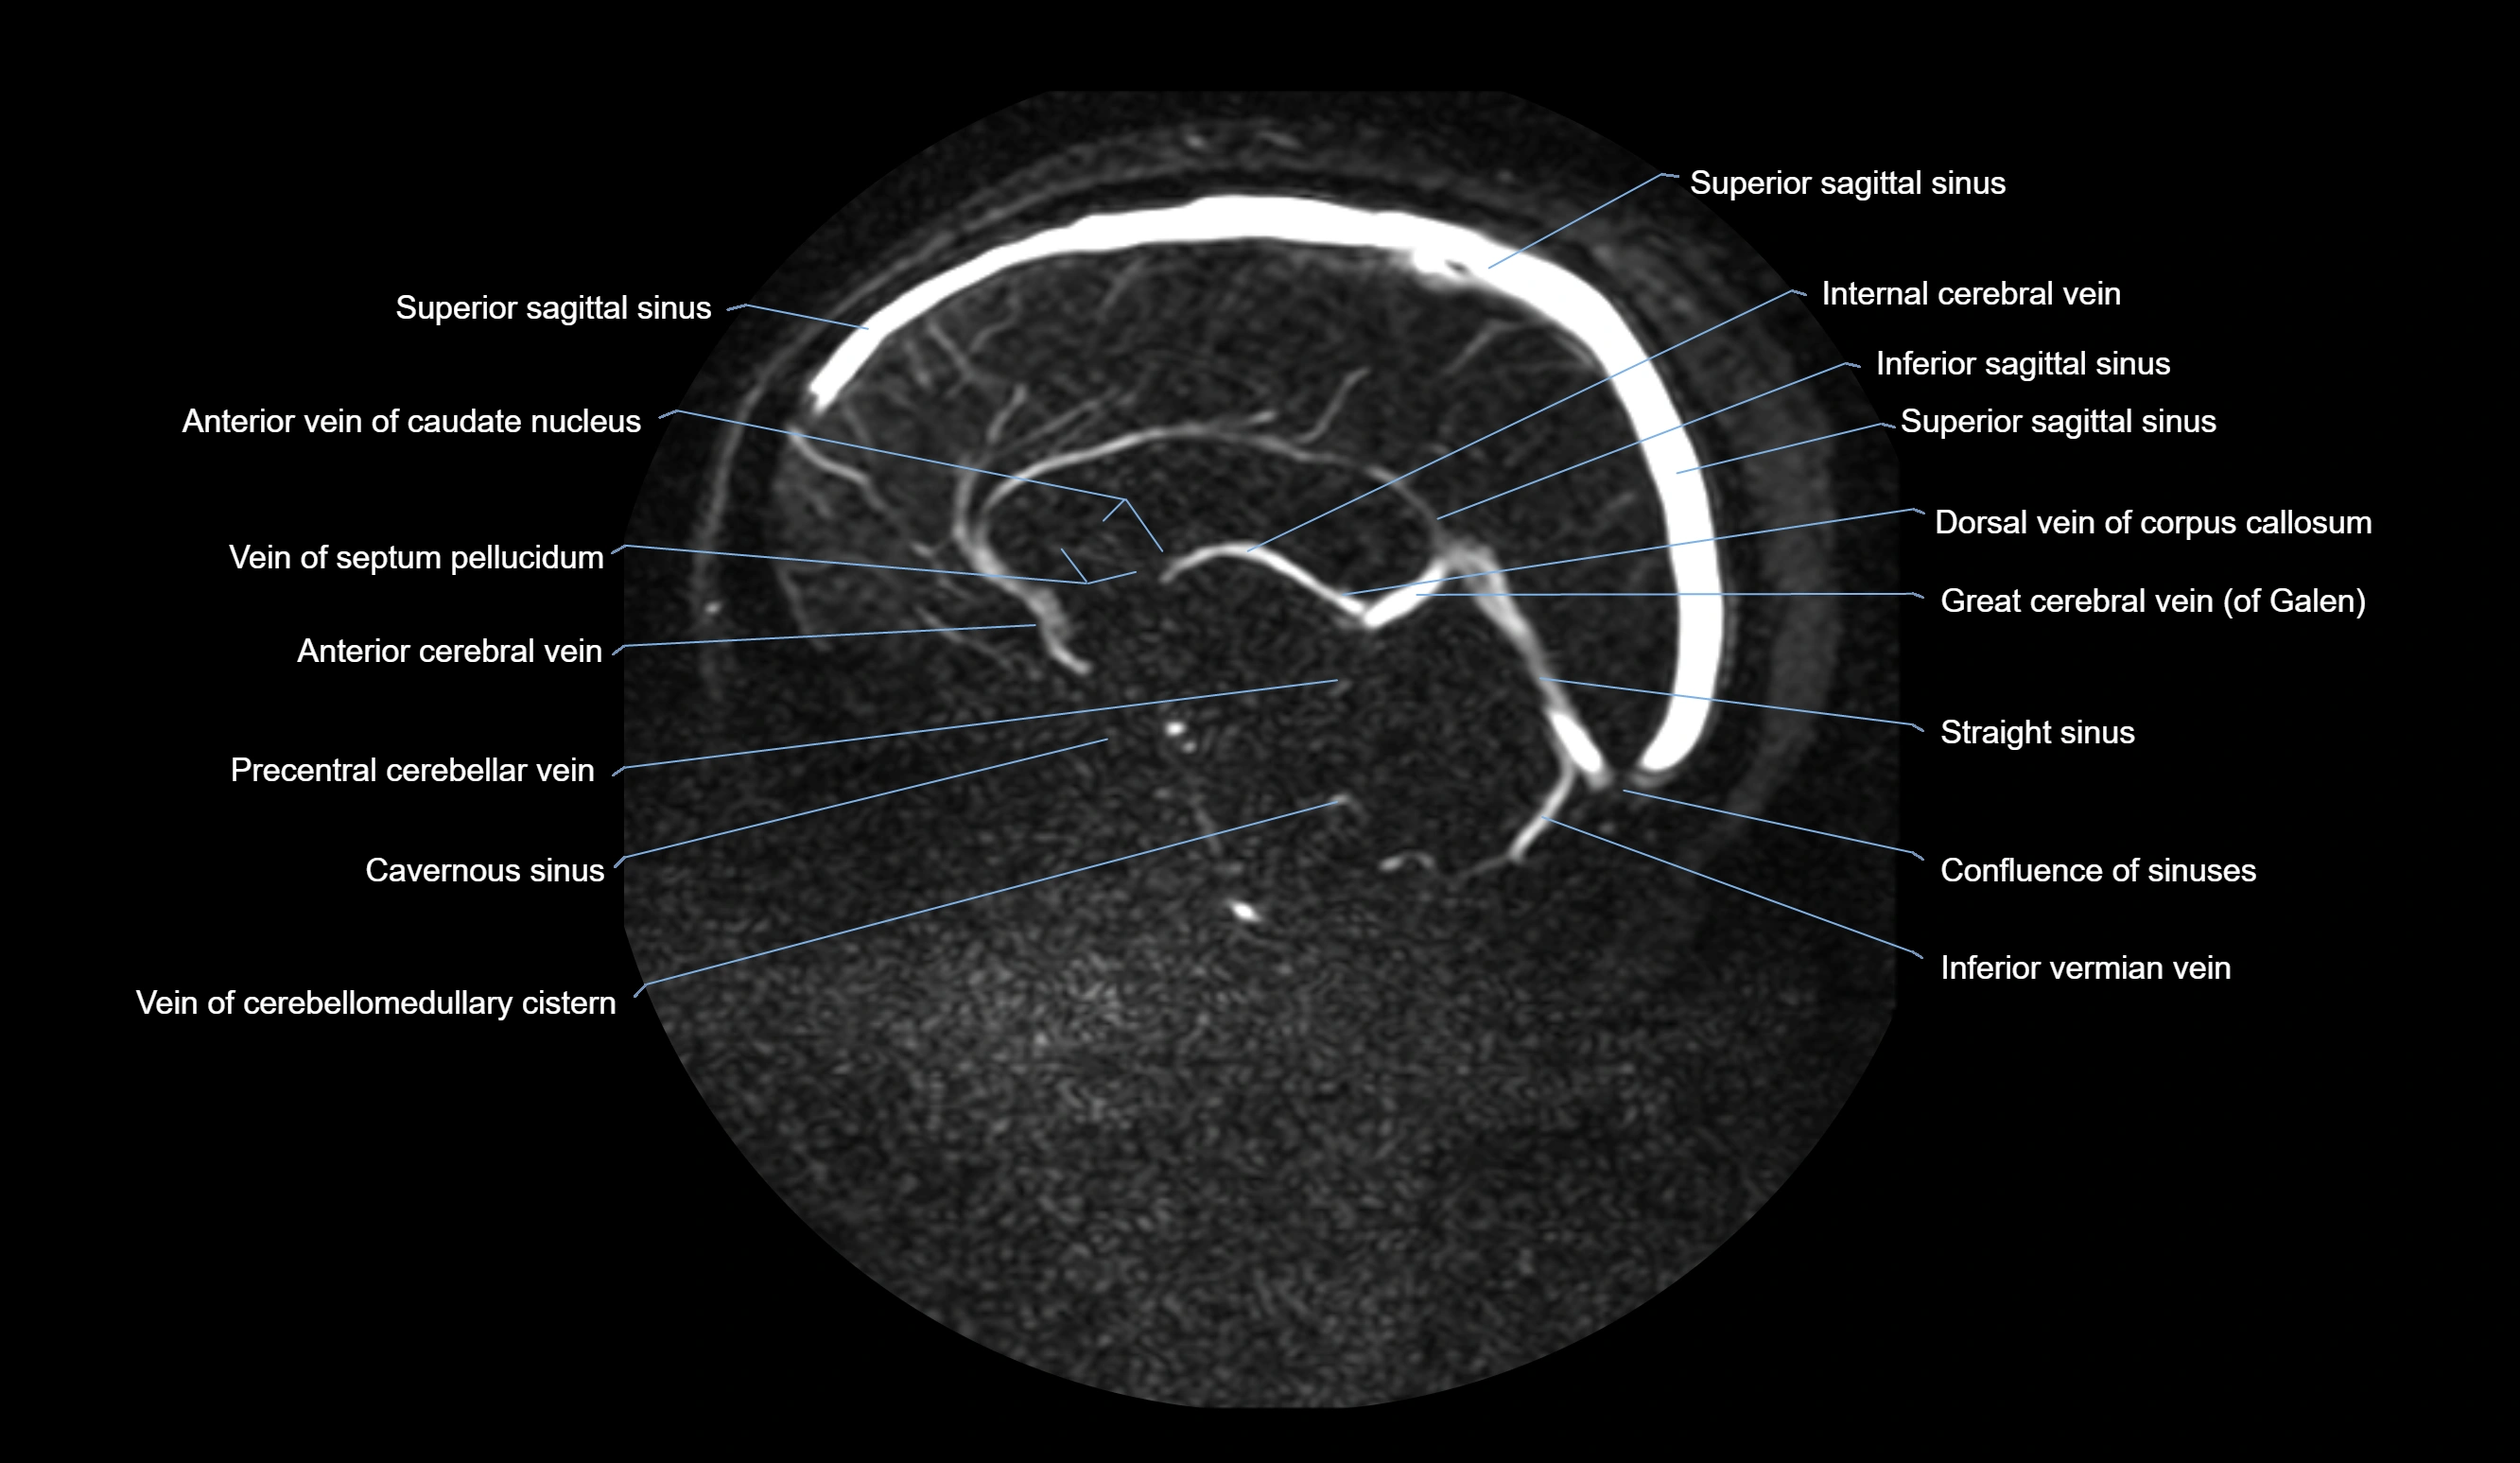

MR Venography (MRV):

• Time-of-flight (TOF) or contrast-enhanced MRV shows the angular vein as a bright enhancing venous channel

• Clearly demonstrates its continuity with the facial vein and superior ophthalmic vein

• MRV is highly useful in evaluating thrombosis, venous obstruction, or collateral venous drainage

MRI images